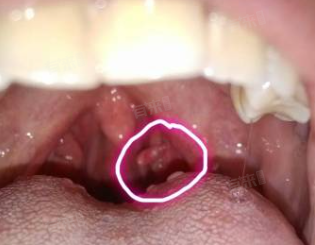

- 喉咙乳头状瘤是一种良性肿瘤,主要由乳头状瘤病毒感染引起,也可由喉部慢性炎症刺激或内分泌失调等因素导致。此种肿瘤通常生长缓慢,边界清楚,不易发生扩散和转移。肉眼观察,喉咙乳头状瘤常呈粉红色,表面有分叶状。

- 若肿瘤较小,且位于喉咙的非关键部位,可能仅表现为轻微的咽部异物感或声音嘶哑,此时病情相对较轻。但若肿瘤较大,或位于喉咙的关键部位,如声带、会厌等,则可能阻塞呼吸道,导致吞咽困难、呼吸困难甚至窒息等严重后果。